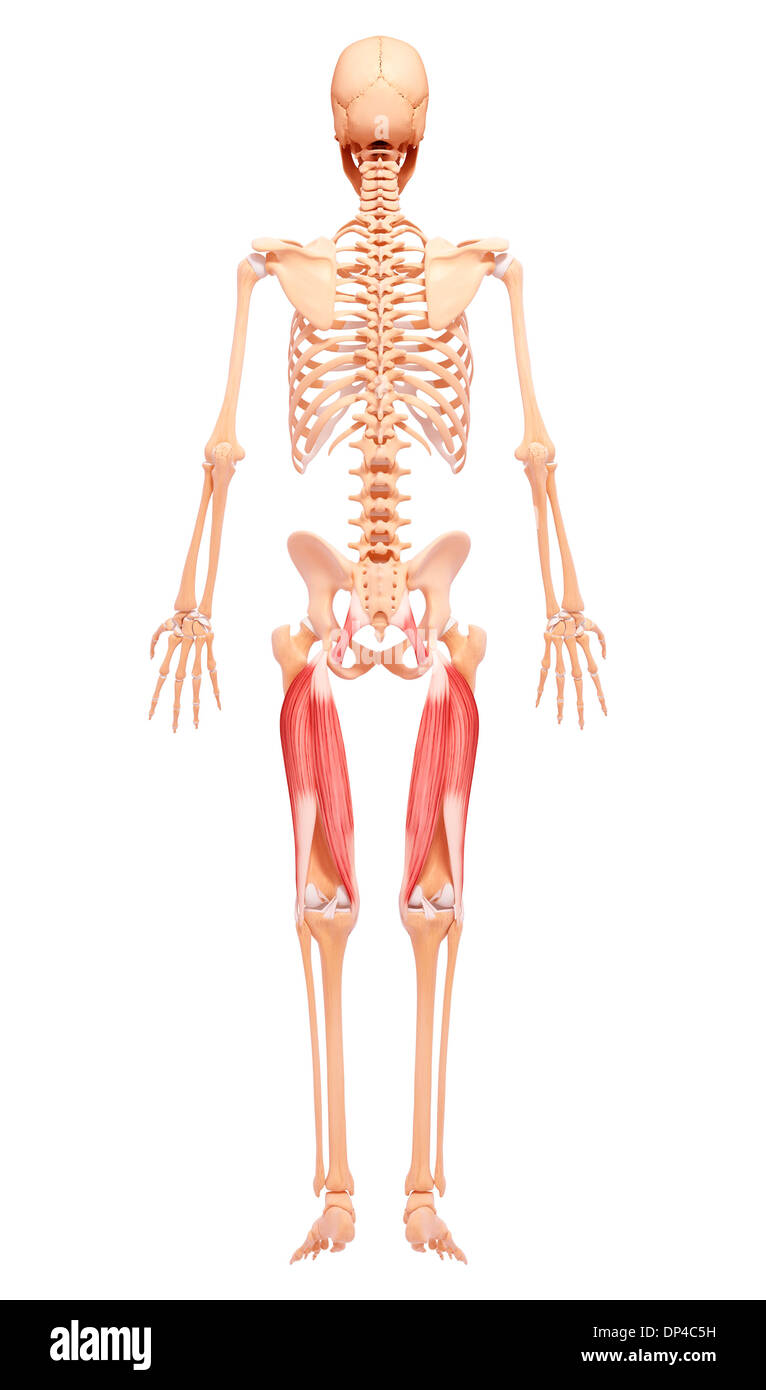

Human foot anatomy, artwork Banque D'Imageshttps://www.alamyimages.fr/image-license-details/?v=1https://www.alamyimages.fr/human-foot-anatomy-artwork-image65250909.html

Human foot anatomy, artwork Banque D'Imageshttps://www.alamyimages.fr/image-license-details/?v=1https://www.alamyimages.fr/human-foot-anatomy-artwork-image65250909.htmlRFDP4C5H–Human foot anatomy, artwork